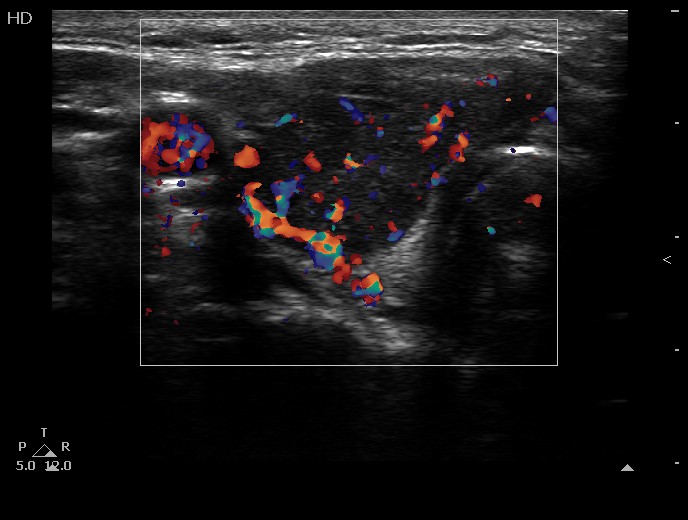

100 consecutive cases of papillary cancer - case 054 (ultrasonographic picture 6)

Right lobe, another transverse scan, color Doppler mode.